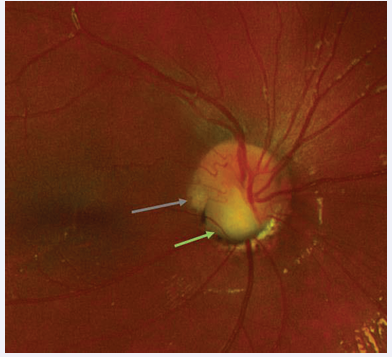

Color fundus photograph shows an ODP on the temporal aspect of the disc and a coloboma, as illustrated in Figure 3,4.

Figure 3 Colour fundus photograph demonstrating ODP on temporal aspect of disc (grey arrow) and coloboma inferiorly (green arrow).